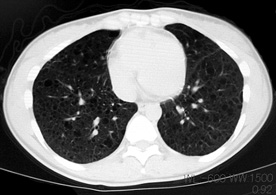

臨床的には進行性肺嚢胞化, くり返す肺気腫, 乳び性胸水貯留が特徴で, 多くの症例では進行性に呼吸不全となる*1

LAM患者さんに認められた両側肺気腫(右図:胸部CT)

firstCT.jpg

secondCT.jpg

初診時CT(左)から2年後のCTでは肺の嚢胞化が著明となっている。